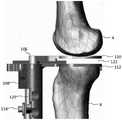

Referring now to fig. 1, a system or procedure for performing one or more steps in knee arthroplasty is shown. Thefemur 4 andtibia 6 are shown with a patient tracking device or dynamic reference fiducial 26 attached to each bone. Thedynamic reference fiducials 26 track the patient's anatomy throughout the procedure. The dynamic reference fiducial 26 may be configured to be tracked by the surgical robot and/ornavigation system 10, such as shown in fig. 2. Surgical robot and/ornavigation system 10 may include, for example, asurgical robot 12, one or morerobotic arms 14, a base 16 (including a computer platform), a display or monitor 20 (and/or an optional wireless tablet, headset, etc.), anend effector 22, and one ormore tracking markers 18.End effector 22 may be configured to secure a catheter, access instrument, or other tool suitable for performing one or more steps in an orthopedic procedure. In one embodiment shown in fig. 2, an access instrument 34 (e.g., a retractor) is attached to theend effector 22 by an articulatedarm 24, and in an alternative embodiment shown in fig. 3, an instrument holder (e.g., a saw blade configured to swing for cutting bone) for securing asurgical saw 36 is connected to theend effector 22. It should be understood that suitable instruments or devices may be connected to endeffector 22 for control byrobot 12.

The surgicalrobotic system 10 may include one or more patient tracking devices ordynamic reference fiducials 26, 130 including one ormore tracking markers 18 adapted to be secured directly to the patient 2 (e.g., to a bone of the patient 2). In the embodiment shown in fig. 1, a first patient tracking device or first dynamic reference standard 26 is fixed to thefemur 4 and a second patient tracking device or second dynamic reference standard 26 is fixed to thetibia 6 of thepatient 2. In this manner, thesystem 10 is able to track thefemur 4 andtibia 6 throughout the procedure.

As shown in fig. 13, the dynamic reference standard 26 is rigidly connected to the patient'stibia 6 andfemur 4. During registration, the patient's anatomy is registered to thesystem 10 and tracked by the dynamic reference fiducial 26. Once the patient is registered, the surgeon may perform a first resection. After cutting, thetensioner 102 may be used to evaluate the gap balance. In the embodiment shown in fig. 13, theproximal tibia 6 is resected and thetensioner 102 is placed against the resection while the bone remains flexed. In fig. 15, theproximal tibia 6 is resected and thetensioner 102 is placed against the resection while the bone is held in extension. It should be understood that resection may be performed after femoral or tibial-first approach.